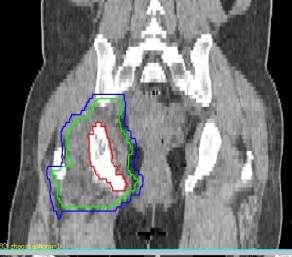

患者赵xx,女,42岁,MR:右侧髋臼窝及坐骨内异常信号,邻近肌肉及股骨小转子区域不同程度受侵。CT:右肺下叶见片状高密度影,气管及主支气管开口通畅,纵隔见结节状软组织影,较大者短径为13mm。右侧坐骨及右侧髋臼密度减低,形态欠规整。临床诊断:右肺下叶腺癌(cT2N2M1 Ⅳ期),纵隔淋巴结转移,多发骨转移。患者腰骶部疼痛明显,疼痛致活动受限,轮椅推入病房。2016年6月给予姑息减症放疗,靶区包括右侧骨盆转移灶(右股骨上段、右坐骨、右耻骨、右髂骨后段),6MV-X线调强放疗,单次量4Gy,放疗组织剂量24Gy/6次/8天。放疗后患者疼痛缓解,现行动自如。